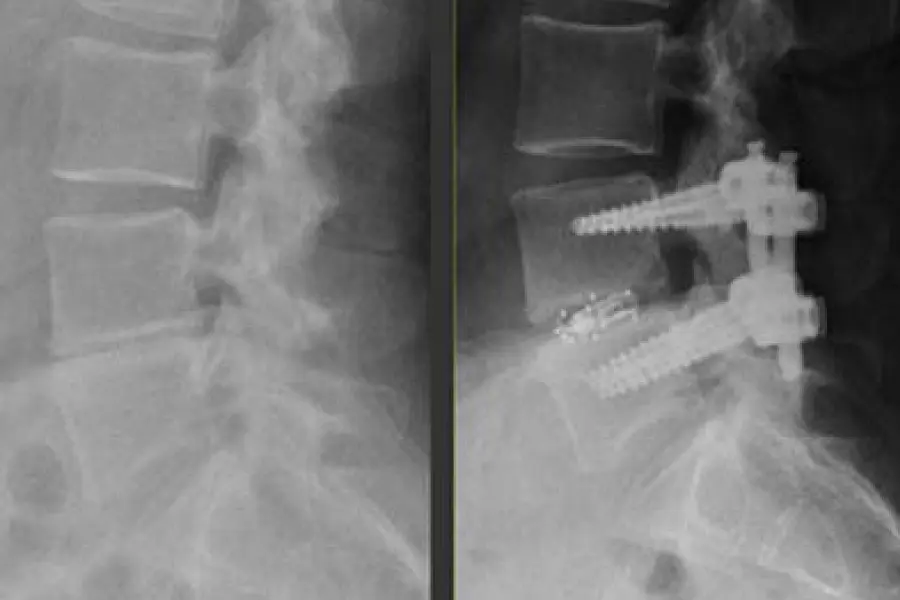

Pushing the Boundaries of Spine Surgery with TLIF

Dr. Ibrahim Hussain, a neurological spine surgeon at Och Spine at NewYork-Presbyterian, performed the first 3D-navigation-guided endoscopic transforaminal lumbar interbody fusion (TLIF) in New York City. This innovative procedure for treating lumbar degenerative pathologies relies on 3D navigation to map a trajectory that avoids nerve injury and helps customize the size of the implant. A collapsed interbody “cage” is expanded after placement inside the disc space under endoscopic visualization. In contrast to open TLIF and minimally invasive TLIF, 3D endoscopic TLIF requires a smaller incision, minimal bone and muscle dissection, and less sedation, resulting in a faster and less painful recovery.

Preoperative and postoperative X-rays